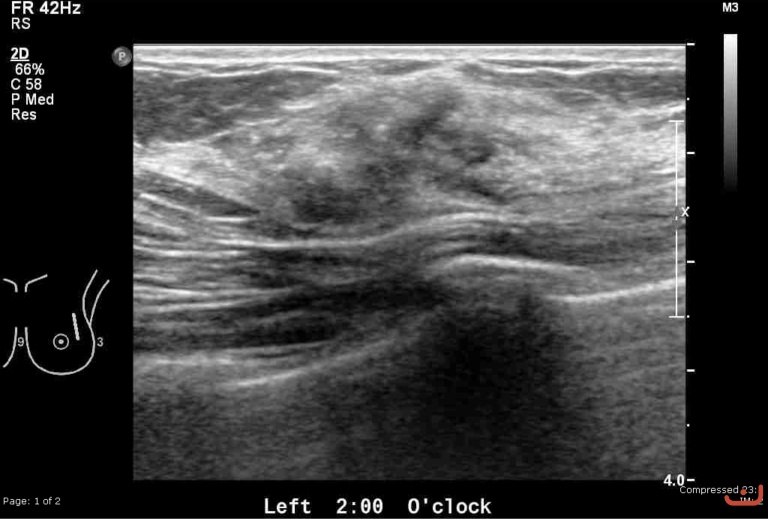

Malignant solid mass

Date

Thursday, 30 April 2015